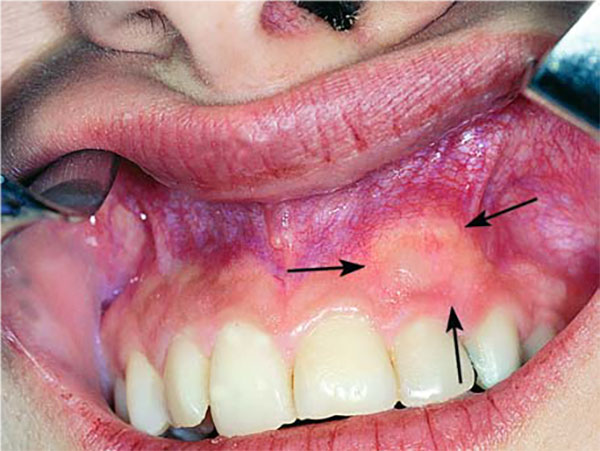

تصویر فوق نمونه ی بیماریست که به اینجانب با مشکل تورم در کام مراجعه کرده است.

حاشیه ی تومور توسط رنگ نارنجی مشخص شده است.

تومور باعث تحلیل ریشه های دندان های اطراف شده است.